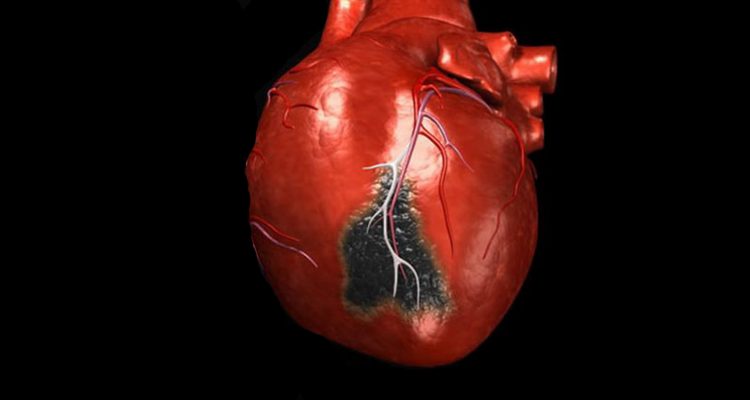

Інфаркт міокарда – це некроз (омертвіння) тканин серця. Він з’являється, коли з якихось причин кров перестає надходити до серцевого м’яза (міокарду). Через брак кисню ділянки серця починають відмирати.

Найчастіше причиною стає звуження артерій, які живлять серце – наприклад, через холестеринові бляшки. Такий стан називають ішемічною хворобою серця. Щоб ішемічна хвороба трансформувалася в інфаркт, іноді не потрібно ніяких провокуючих чинників: досить прокинутися і встати з ліжка, щоб бляшка розірвалася, а тромб, який утворився заблокував кровоносну судину. При стресі або незвичній фізичному навантаженні цей ризик зростає.